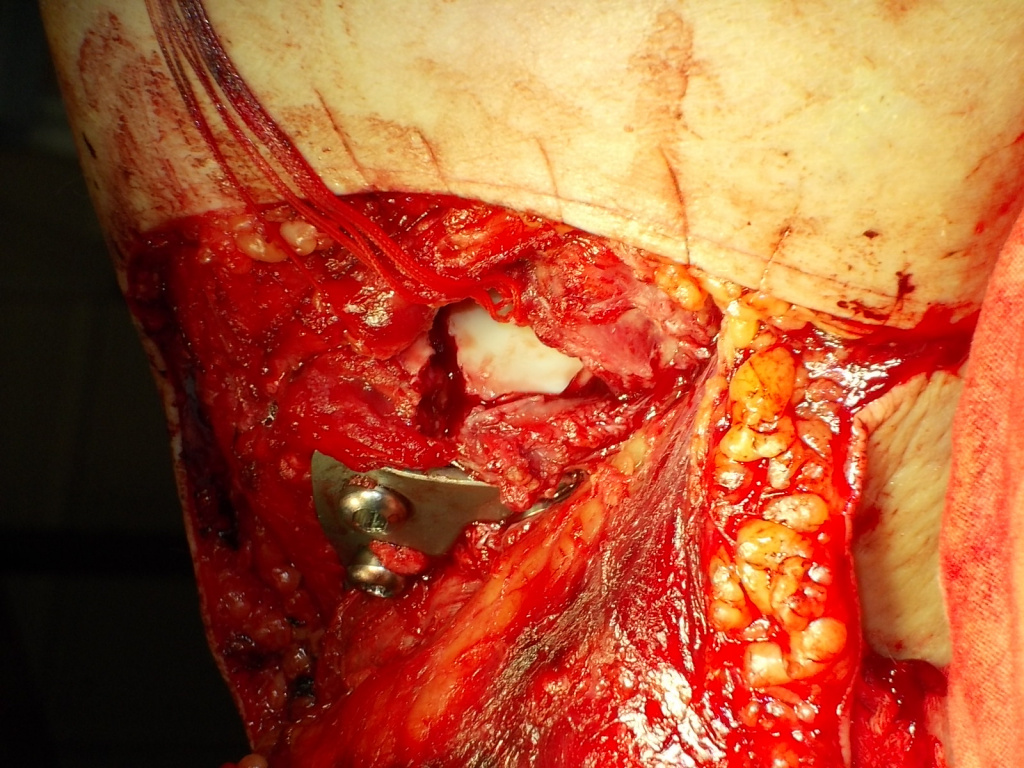

Использование материала Остеоматрикс при импрессионном оскольчатом переломе наружного мыщелка большеберцовой кости по типу Schatzker II

Использование материала Остеоматрикс при импрессионном оскольчатом переломе наружного мыщелка большеберцовой кости по типу Schatzker II.

Операция - открытая репозиция, остеосинтез большеберцовой кости опорной пластиной с костной ксенопластикой маетриалом "Остеоматрикс". На контрольных снимках в три и шесть месяцев имеется консолидация перелома, миграции фиксатора нет, имеется остеоинтеграция ксенопластического материала. Функция коленного сустава полная.